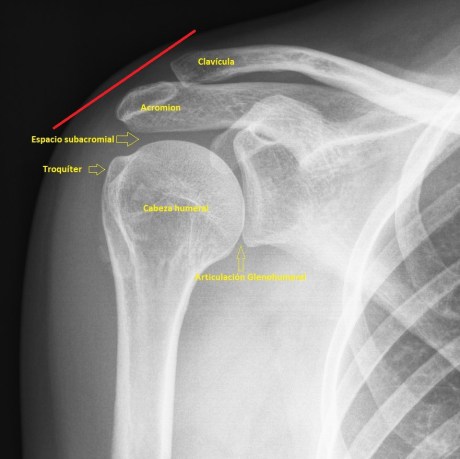

La anatomía radiológica que interviene es este estudio específico de la maniobra dinámica del tendón del supraespinoso te la dejo aquí.

1

Una vez que hayas visto el vídeo explicativo de youtube y revisado la anatomía radiológica de la imagen 1, quiero que aprendas a realizar la maniobra, imagen 2 y 3, con la que vamos a estudiar el tendón del supraespinoso a su paso por el espacio subacromial, que es, realizando una abducción del brazo partiendo desde la posición de reposo del húmero justo al costado y llevándolo mediante dicha abducción hasta los 90º del húmero con respecto al costado…mira:

Es importante tener localizado ecográficamente la articulación acromio clavicular (AAC) con la ecografía, posicionando el transductor, línea roja, como ves en esta imagen 4, donde debes cubrir toda la anatomía radiólogica explicada antes, mira: